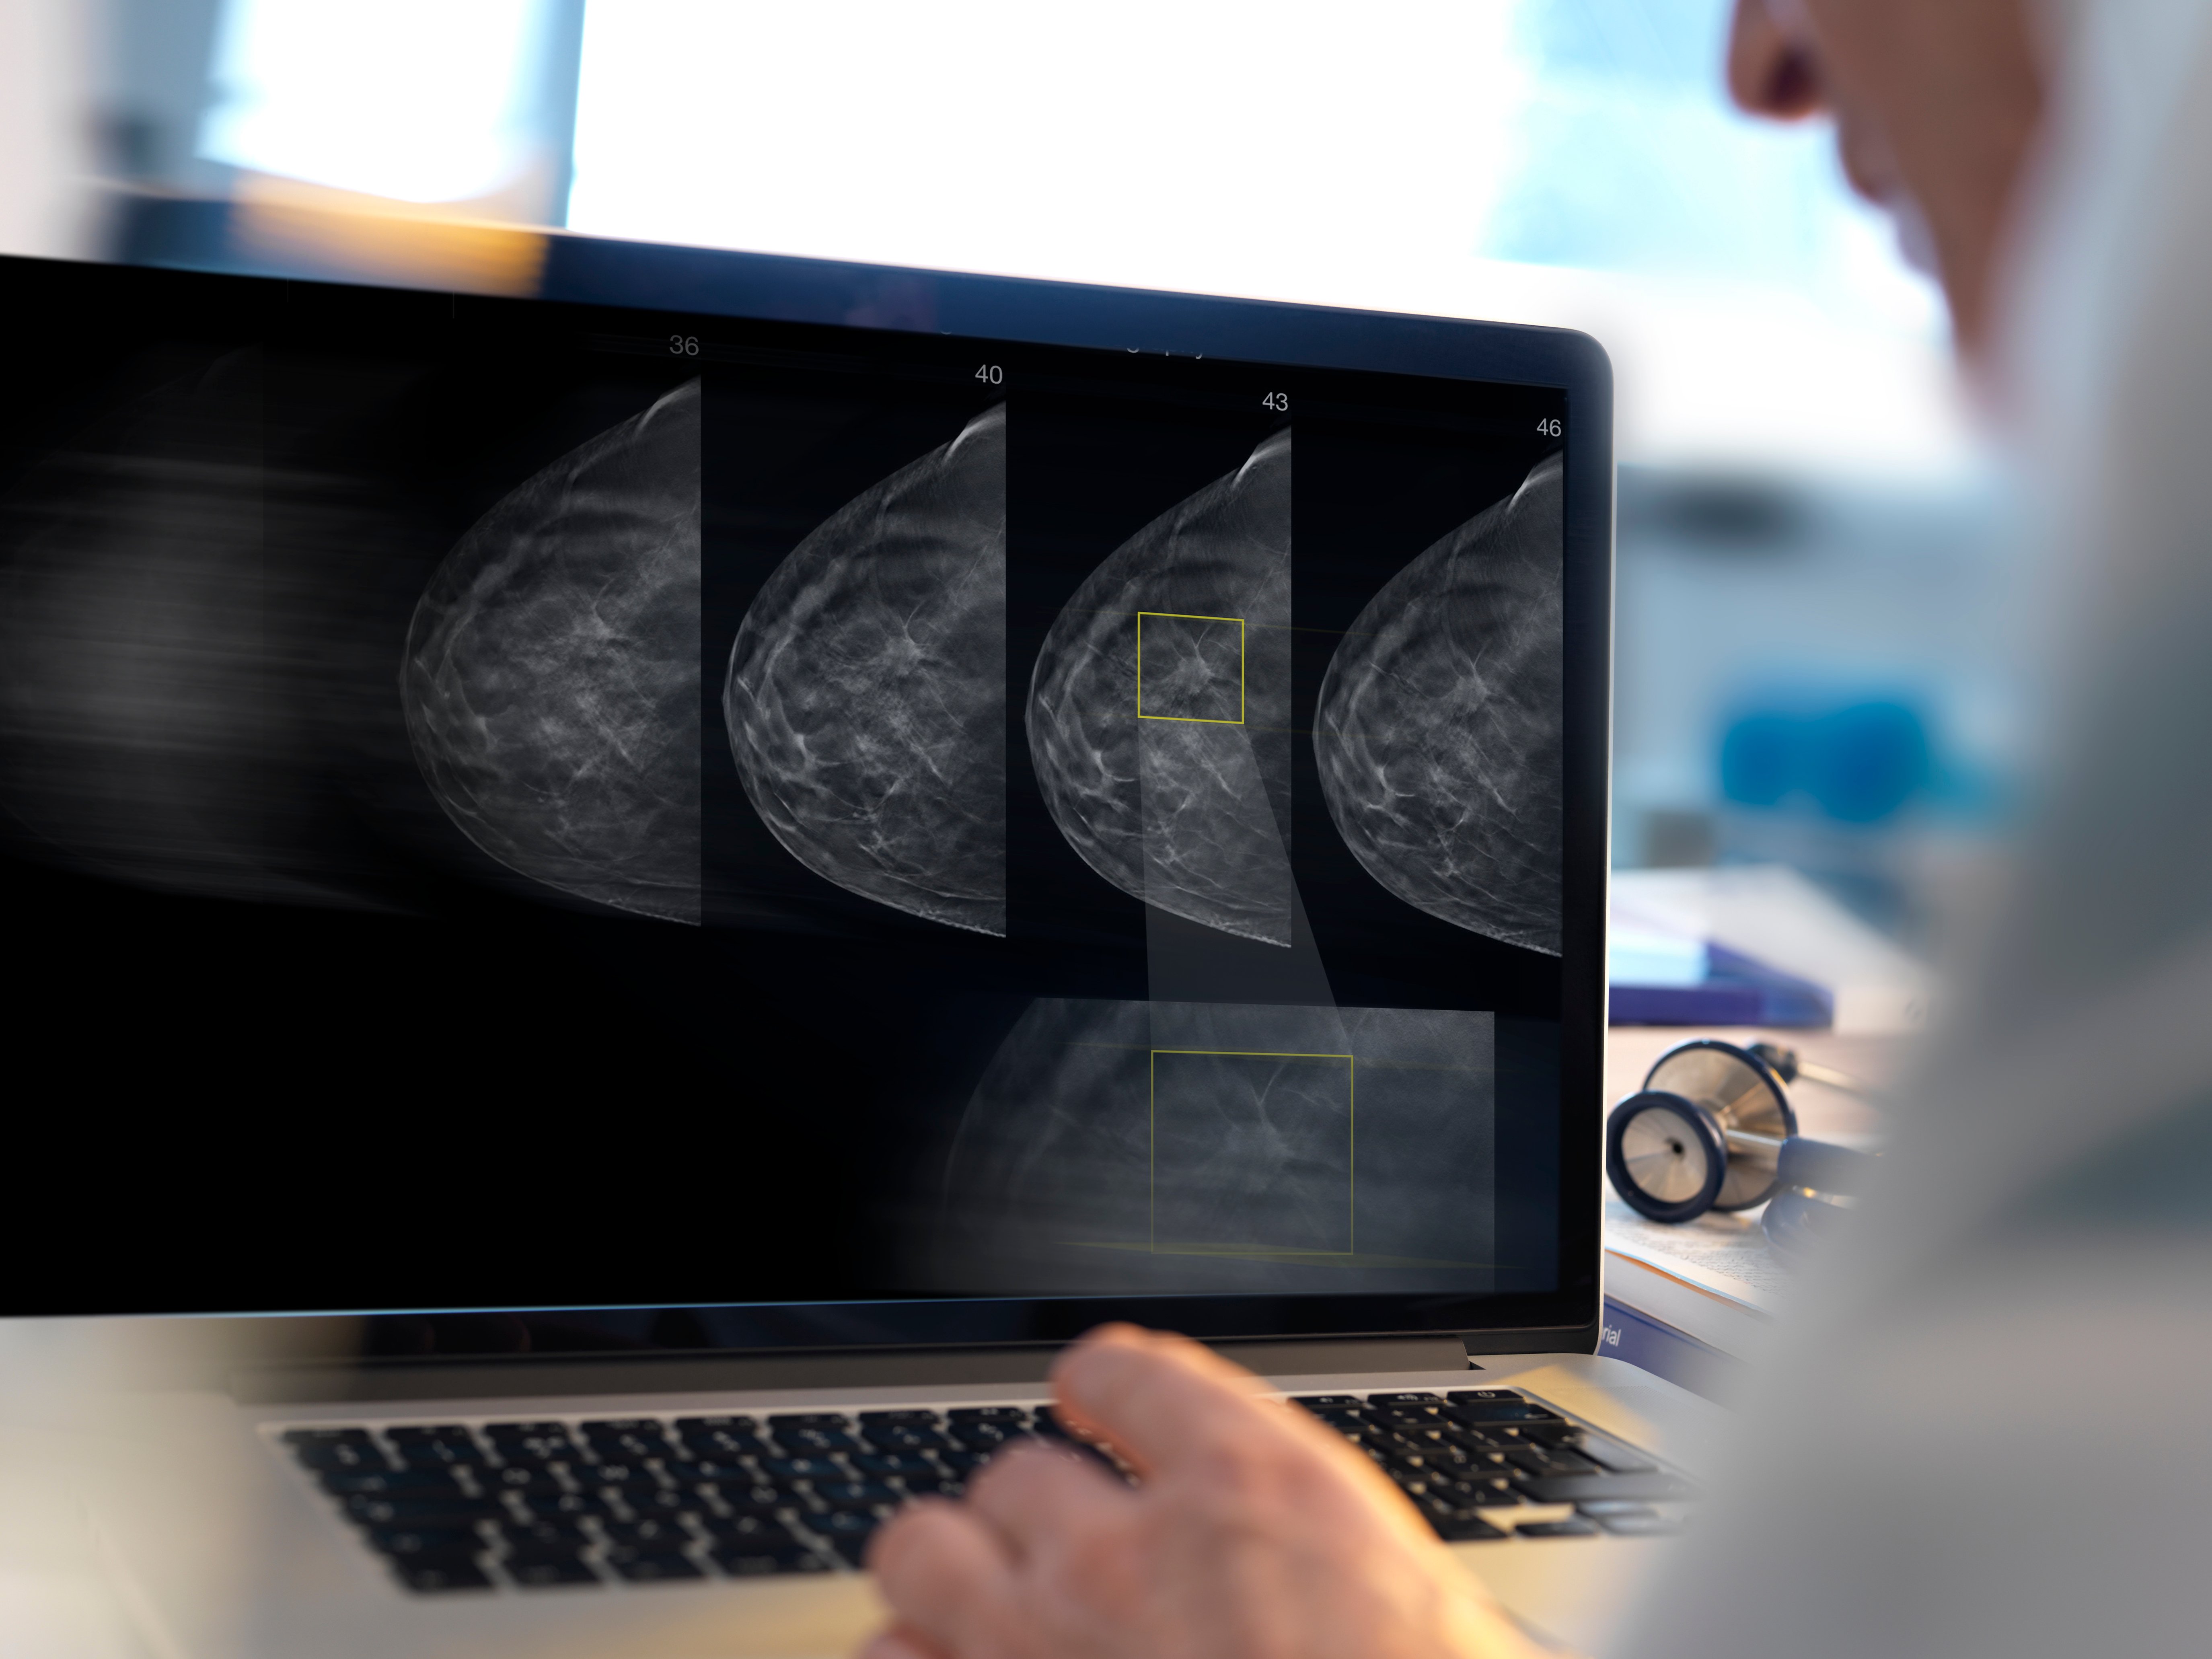

Getty Images

Mammography is one of the great triumphs of innovation in breast cancer care, as it is the only screening technology proven to decrease the breast cancer mortality rate. It is the essential tool in a radiologist’s toolkit for breast cancer screening and detection. Despite that success, it has known limitations the industry has been working to overcome since the technology first debuted with the goal of increasing early invasive cancer detection while reducing false positives.

The most notable outcomes of DBT adoption have been significant improvements in detection and reductions in recall rates. Take for example the 3Dimensions mammography system from Hologic, which has been shown to detect 20 to 65% more invasive cancers than a 2-D mammogram alone1 and has also been FDA approved as superior to 2-D mammography for women with dense breasts.1, 2 Furthermore, the DBT system also reduces false positive rates compared to full field digital mammography,3 which has the potential to not only spare women the emotional toll of unnecessary callbacks but also reduce the economic impact on the healthcare system.

A malignancy easily missed with conventional 2-D mammography was clearly seen with Hologic 3-D Mammography.